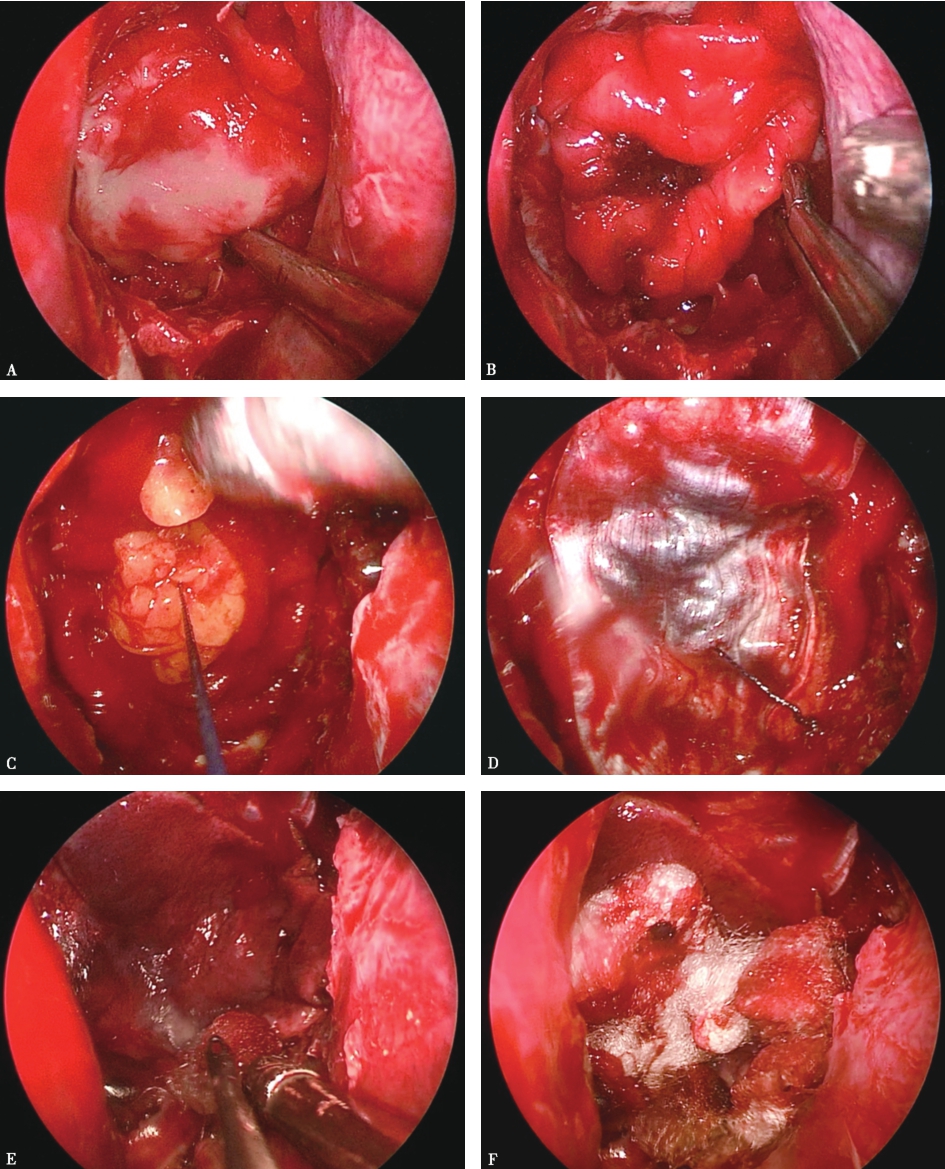

图2神经内镜下切除侵袭右侧海绵窦的垂体腺瘤

A.高速磨钻磨开鞍底骨质,显露鞍底及右侧海绵窦腹侧壁的硬膜,显露范围根据肿瘤大小和生长方向而定;B.多普勒超声探头探测右侧海绵窦内颈内动脉的位置(箭头);C.内镜下切开鞍底硬膜,切除鞍内肿瘤后显示右侧海绵窦内侧壁缺损(*);D.神经内镜下进一步显露并切除右侧海绵窦内颈内动脉外侧肿瘤(#),颈内动脉完全游离,充分反映神经内镜下显露充分的优势。a.前曲;b.水平段;c.后曲;C.颈内动脉隆起;Cl.斜坡;CS.海绵窦;ICA.颈内动脉;S.鞍底

图3手术结束

A.先用人工硬膜覆盖鞍膈;B.然后选用可吸收止血材料填充鞍内,鞍内的填充可以起到压迫止血的作用,但鞍内填充一定要适量,若过度填充,则可能对视交叉、双侧海绵窦造成压迫,导致视交叉及海绵窦神经受损伤;C.若患者为明显脑脊液漏,鞍内填充可选用自体脂肪组织;D.再用足够大小的自体筋膜覆盖鞍底。自体脂肪的优势在于,在一定时间内起到支撑、填充的作用,不产生排斥反应,可起到隔绝脑脊液的作用,为鞍底愈合创造条件及时间;E.在蝶窦腔,先用带蒂的鼻中隔黏膜瓣覆盖整个蝶窦后壁,黏膜瓣在手术早期取材时就必须考虑到长度及宽度,若黏膜瓣大小不够,则可和自体筋膜相互配合,务必将手术开放的蝶窦后壁完整覆盖;F.蝶窦填塞主要起到支撑颅底重建的复合材料的作用,如果没有脑脊液漏,可用可吸收的材料进行蝶窦填塞,如:可吸收凝胶海绵等。如果是明显脑脊液漏的病例,可采用碘仿纱条或尿管水囊对重建材料进行支撑,待颅底愈合后再将支撑材料撤走